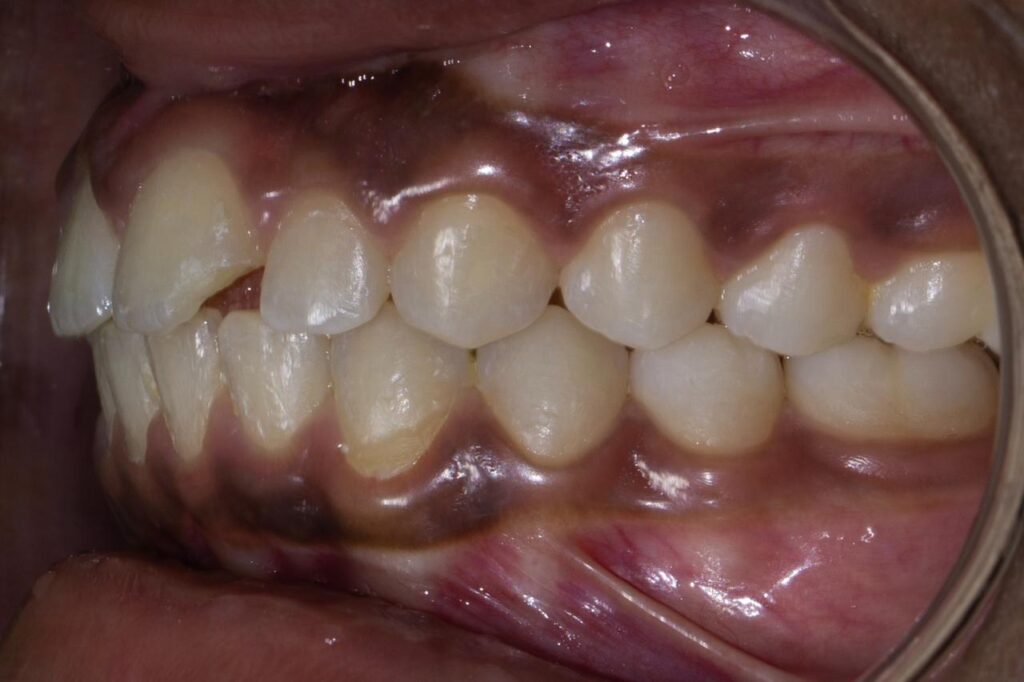

Fix misaligned teeth with braces or aligners through expert orthodontic treatment in Baner, Pune.